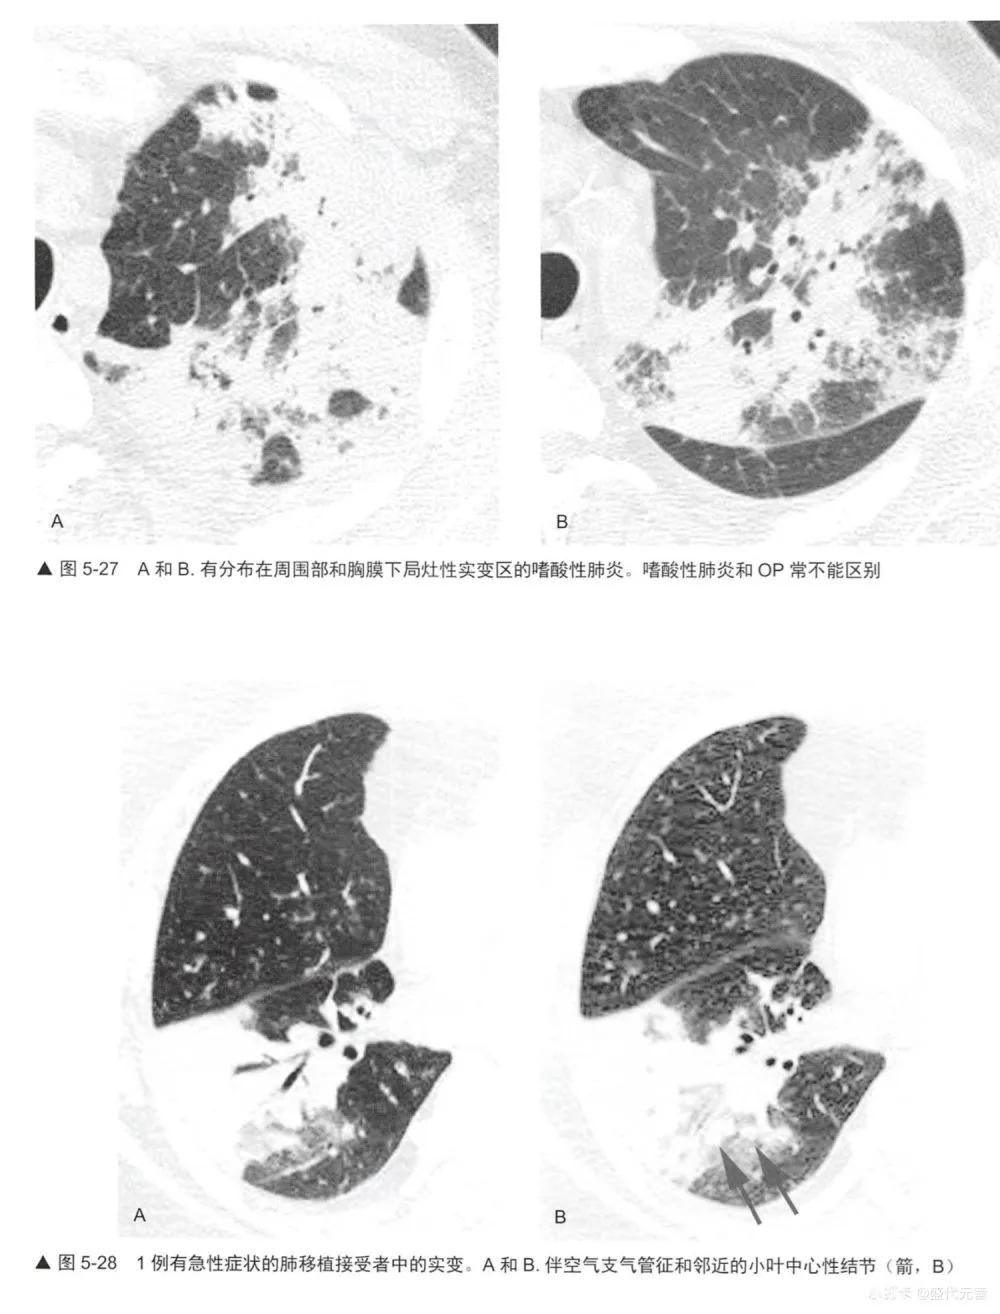

实变是指肺衰减增加并掩蔽了肺血管(图5-1,图5-24〜图5-28)可有空气支气管征(图5-28)。如胸片上已可见明确的实变证据时,HRCT对病例的诊断几乎无帮助。无论如何,HCRT可在胸片有诊断性之前检出实变。实变可伴有局灶性磨玻璃影和小叶中心性结节(图5-28,图5-29)。

实变的鉴别诊断与磨玻璃影(表5-1)有相当大的重叠,事实上,许多表5-1列出的疾病都显示为这两种表现的混合(表5-5)。实变的鉴别诊断包括不同原因的肺炎:最典型的是细菌性(图5-28),但也包括分枝杆菌、真菌性肺炎(图5-29)、支原体、耶氏孢子菌和病毒性肺炎; 0P (图5-24和图5-25);嗜酸性肺炎(图5-26,图5-27),如NSIP和DIP的间质性肺炎;HP (图5-30);放射性肺炎、浸润性黏液腺癌(图5-16和图5-31); LIP;淋巴瘤(图5-32)和淋巴增生性疾病;肺泡蛋白沉着症;结节病;药物反应,肺水肿和肺出血;AIP, DAD和ARDS。与吸入动、植物油脂或矿物油有关的外源性类脂性肺炎,可导致磨玻璃影或实变,此时因含有脂肪是低衰减的(图5-33)。